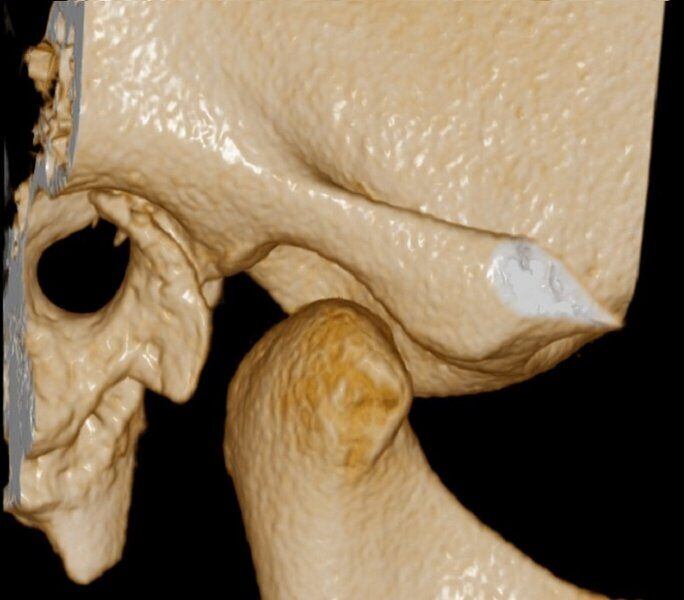

ATM Bocca Aperta